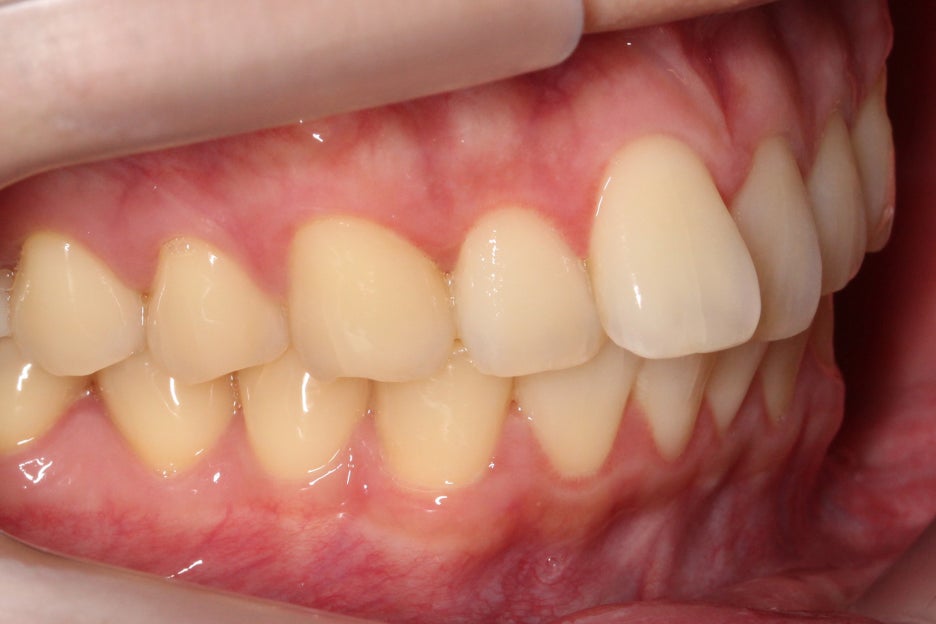

교정 후 협측 모습을 보면 전치부 치열이

돌출된 곳 없이 고르게 바뀐 모습을

확인할 수 있는데요,

문제가 있던 중절치가 개선되어

전치부의 스마일라인도 정돈된 모습입니다.

논현동치과 윗니부분교정 후 치아의 배열을 보면

바깥으로 누워있듯이 뻐드러져 있던

11번 치아가 자연스럽게

교정된 것을 확인할 수 있으며

전체적인 안모의 모양도 곡선을 그리며

U-모양으로 형성되어 있어 심미적인 모습인데요,

치아가 배열된 모습이 U-모양에 가까울수록

이상적인 안모가 될 수 있습니다.